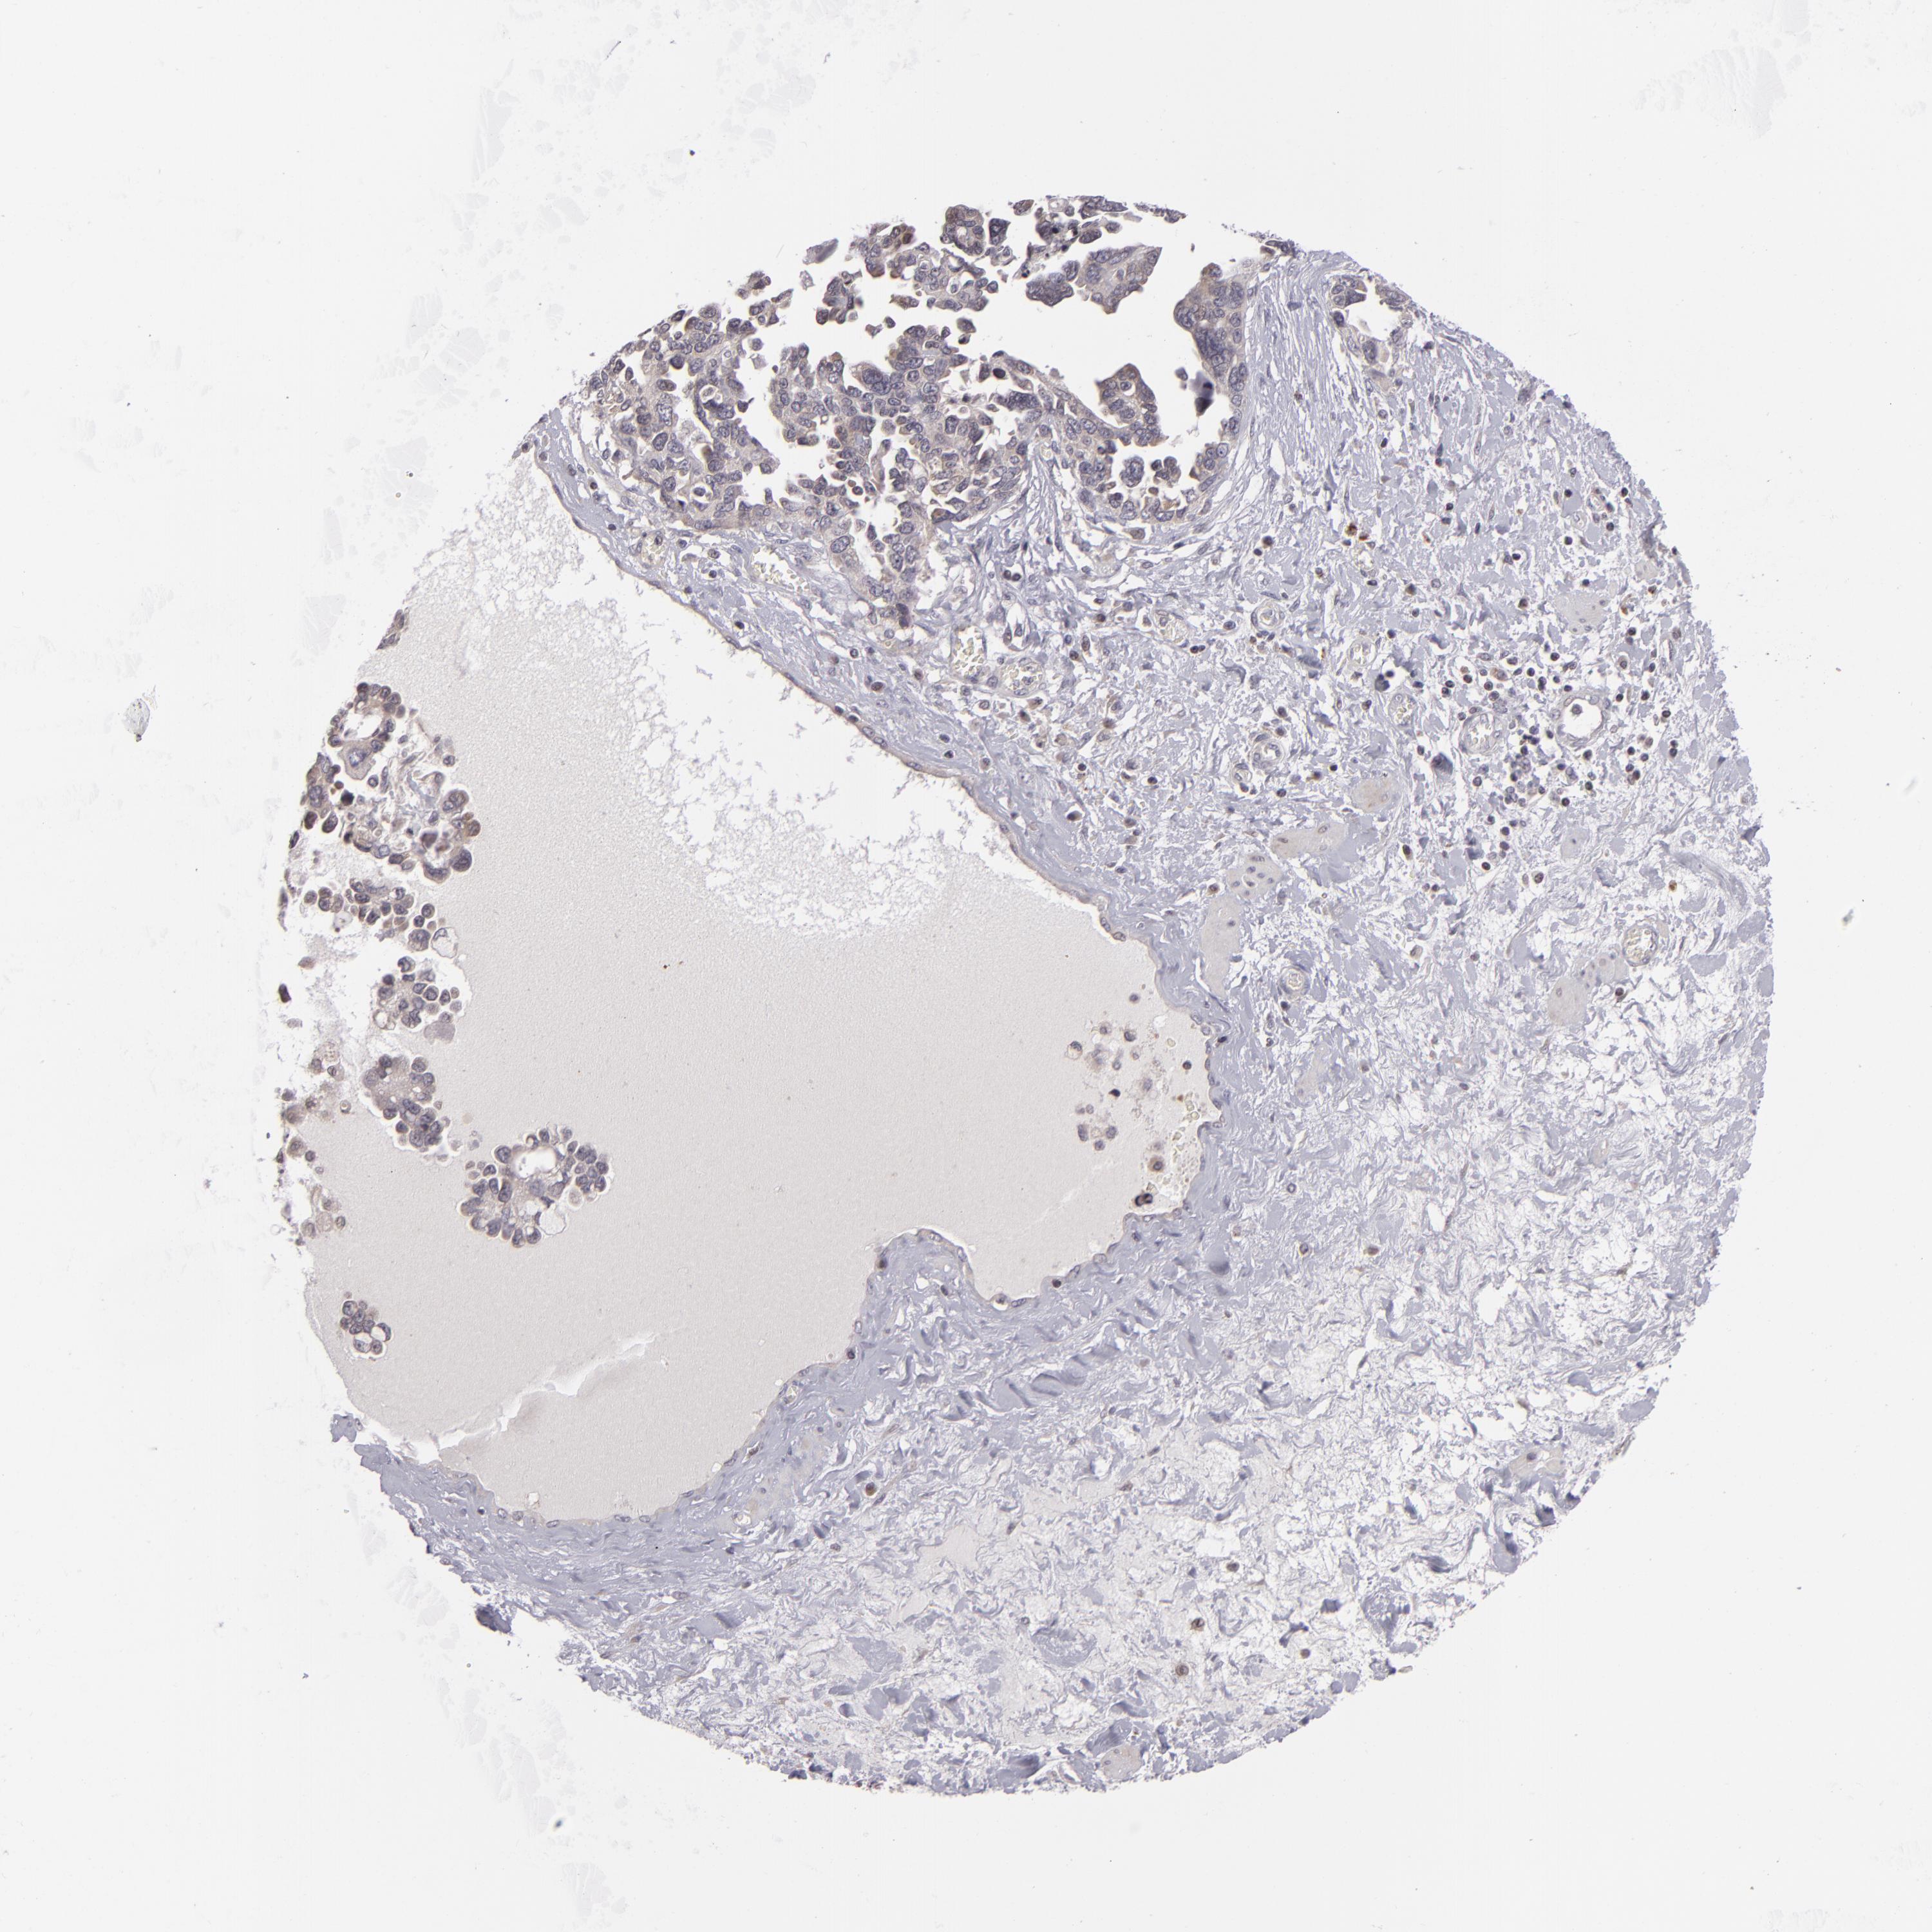

OVARIAN CANCER - Protein expressioni

A mouse-over function shows sample information and annotation data. Click on an image to view it in a full screen mode. Samples can be filtered based on level of antibody staining by selecting one or several of the following categories: high, medium, low and not detected. The assay and annotation is described here.

Note that samples used for immunohistochemistry by the Human Protein Atlas do not correspond to samples in the TCGA dataset.

Antibody stainingi

Antibody staining in the annotated cell types in the current human tissue is reported as not detected, low, medium, or high, based on conventional immunohistochemistry profiling in selected tissues. This score is based on the combination of the staining intensity and fraction of stained cells.

Each image is clickable and will lead to virtual microscopy that enables deeper exploration of all samples and also displays staining intensity scores, fraction scores and subcellular localization as well as patient and tissue information for each sample.

Antibody HPA048741

Antibody CAB001983

Cystadenocarcinoma, serous, NOS

Carcinoma, NOS

Cystadenocarcinoma, mucinous, NOS

Carcinoma, endometroid